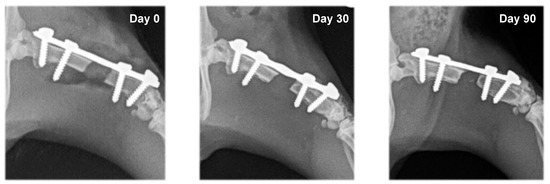

3.2. Radiography